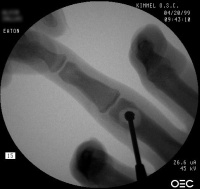

| Case 1. This 18 year old man

presented with a two year history of pain and swelling of the distal

aspect of his proximal phalanx. |

| Plain films showed

sclerosis within a radiolucent area and adjacent cortical/endosteal

sclerosis. |